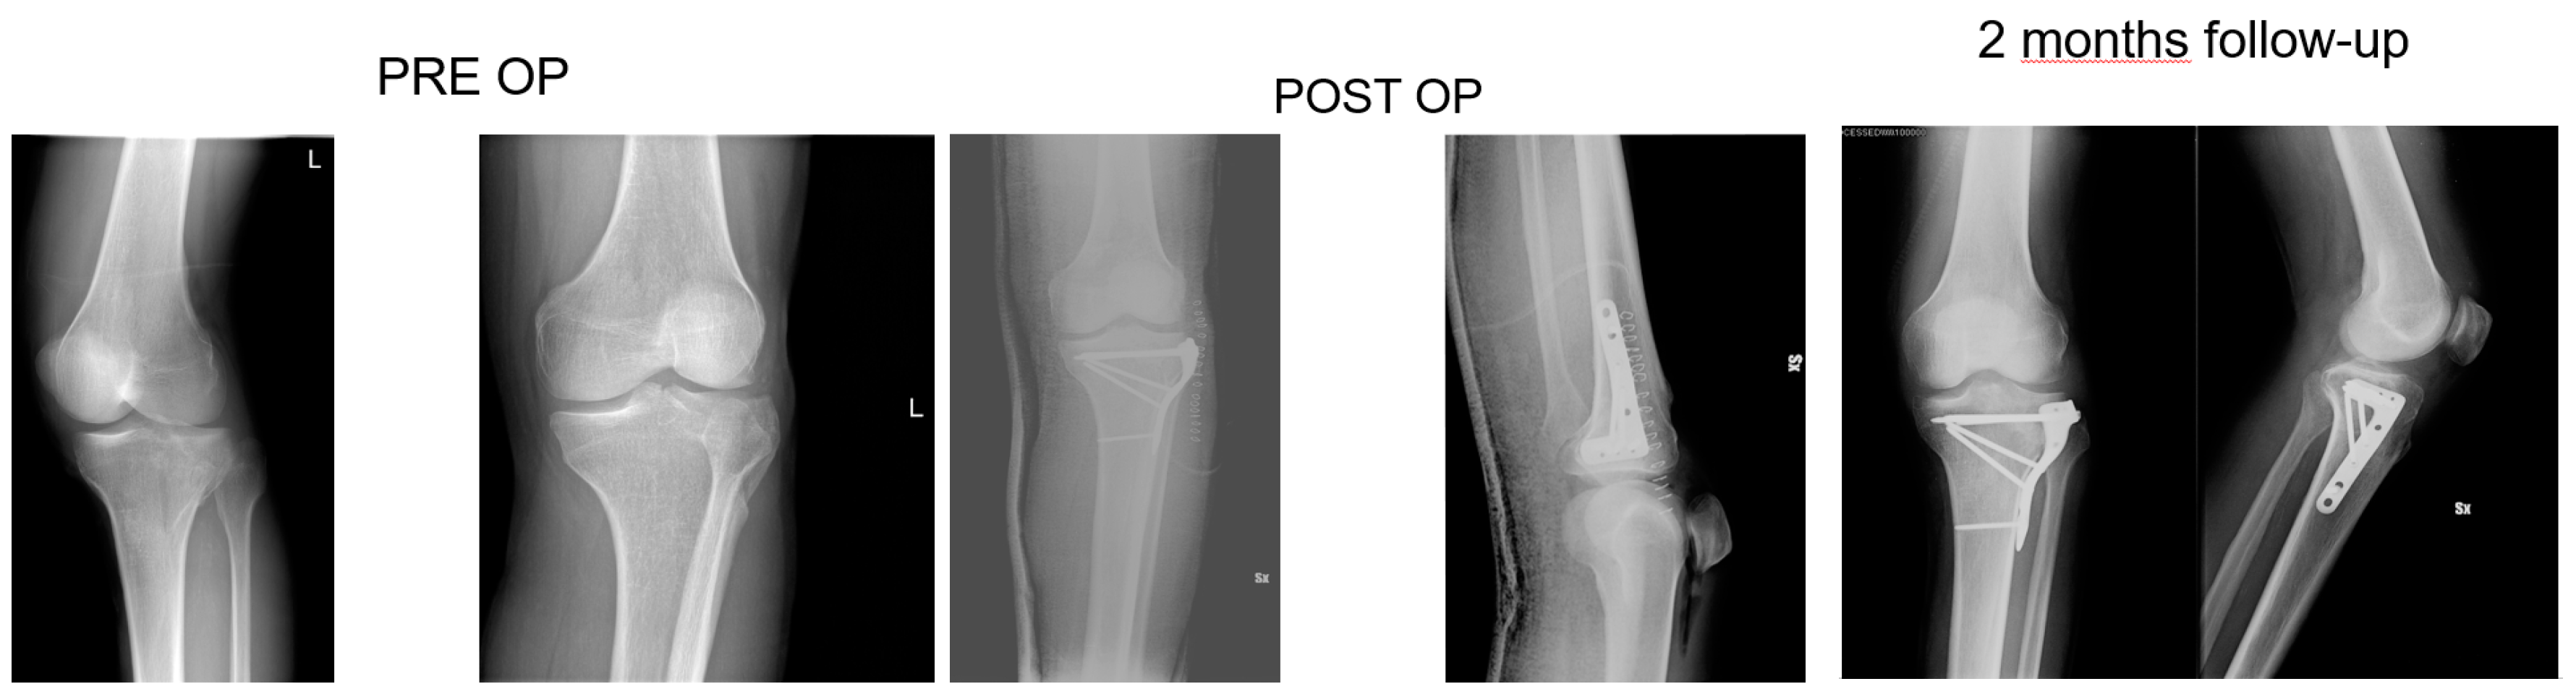

Figure 3. 68 years old patient, X-rays: preoperative, postoperative and control at 2 months follow up of a Shatzker type 2 fracture, AO 41 B1.3.

All patients had surgery within 48 hours from injury, after administration of spinal or general anaesthesia. A tourniquet was routinely positioned before starting surgical procedure; all patients were operated in a supine position, with injured leg in semi-flexion. Fractures were reduced through a percutaneous or open approach, depending on the cases; SB blocks, which size and shape were customised during surgery considering the features of bone defect for each singular patient, were positioned through a minimally invasive approach via the bony window exploited for reduction; finally, fixation of fracture line and implant were performed with screws and plates (see exemplificative Figure 1, Figure 2 and Figure 3). In one case fixation of the plateau fracture occurred through an arthroscopic approach. All the patients included in the study had identical post-operative regimen. Active knee mobilization and static quadriceps exercises were encouraged from the third day after surgery. Partial weight bearing was allowed at 4–6 weeks after surgery, and progressively increased to achieve full weight bearing at 12 weeks. Prophylaxis for thromboembolic events was obtained through administration of 4000 IU/day of low molecular weight heparin (LMWH) (enoxaparin), until full weight bearing was allowed.

Patients were clinically and radiologically assessed before surgery, at 2 weeks, and then at 1, 2, and 6 months, and 1 year after surgery. Same radiologist carried out the imaging, while evaluations were pooled by different clinicians. Clinical assessment consisted of a visual analogue scale (VAS) for the evaluation of pain, where patients were asked to report the level of pain during the day life activities; measurement of the range of motion (ROM) of the knee joint; and objective examination, intended to highlight possible alterations of surgical scar, vascular and nervous deficits, as well as infectious complications. Moreover, at 1-year follow-up Tegner Lysholm Knee Scoring Scale [21] and International Knee Document Committee 2000 (IKDC 2000) [22] questionnaires were administered during control visits, in order to evaluate patients’ subjective perception of knee function. One year after surgery, patients answered to the Short Form (36) Health Survey (SF-36) questionnaire, which scores the general physical and mental health on the basis of eight scales each ranging from 0 to 100 [23]. Radiological assessment contemplated the acquisition of anteroposterior and lateral projections radiographs at each follow-up. Images were examined in order to evaluate various features of healing process, like callus formation and maintenance of fracture reduction; as well as to detect the presence of possible malalignment, pseudo-arthrosis, bone non-unions, and articular surface depression or widening (see exemplificative Figure 1, Figure 2 and Figure 3).

At six months, X-rays images showed that all 34 fractures displayed a good consolidation rate, as confirmed by radiological reports. In particular, radiolucency of the xenografts was assessed [20], which became progressively more similar to that of the surrounding healthy bone tissue (see exemplificative Figure 1, Figure 2 and Figure 3 and comparative images in Figure 4).

Comparison with the current literature is challenging, due to the lack of standardised follow-up protocols and differences in quantitative assessment of outcomes among the studies. However, the implant of SB in our series resulted in a standard return to knee mobilisation, as highlighted by the mean ROM at last follow-up and the return to partial weight bearing at 4–6 weeks. We also described no complications, like infections and joint subsidence, if compared to similar studies present in the medical literature [31]. Radiological follow-up did not show diastasis or depressions of tibial articular surface excluding the incomplete subchondral reductions documented at the first post op X-ray, which means that mechanical properties of SB were adequate for high and complex forces which the plateau commonly undergoes. At each follow-up, the radiolucency of implants was progressively more similar to radiolucency of the surrounding bone (see exemplificative Figure 1 and Figure 2). We interpreted this evidence as supporting the thesis that SB would have been able to integrate with autologous bone tissue, favouring deposition of new bone matrix within an ongoing remodelling process: indeed, there is a clear morphological pattern on the evolution of the standard X-Ray imaging series over time which shows the substitution of the grafted material with a more homogeneous signal in the area of graft implant. As already demonstrated, the progressive remodelling together with an increase of the mineral signal cannot be dependent on the active remodelling of the graft per se given it is a decellularized matrix. Therefore, the increase in the density over time depends on novel mineral matrix apposition likely induced by the graft, as previously shown both in vivo and in vitro [7,20].